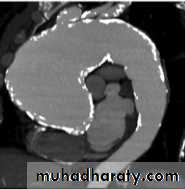

Aortic dissection